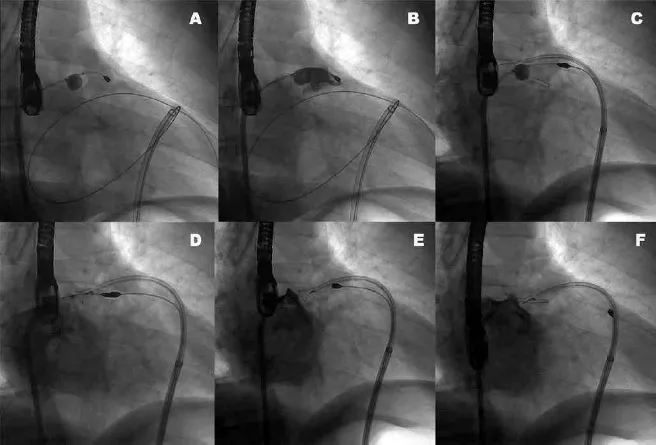

what device is being deployed in this fluoroscopy

device

access

function

Lariat device

Epicardial

Closing t

Identify the structural heart device and access.